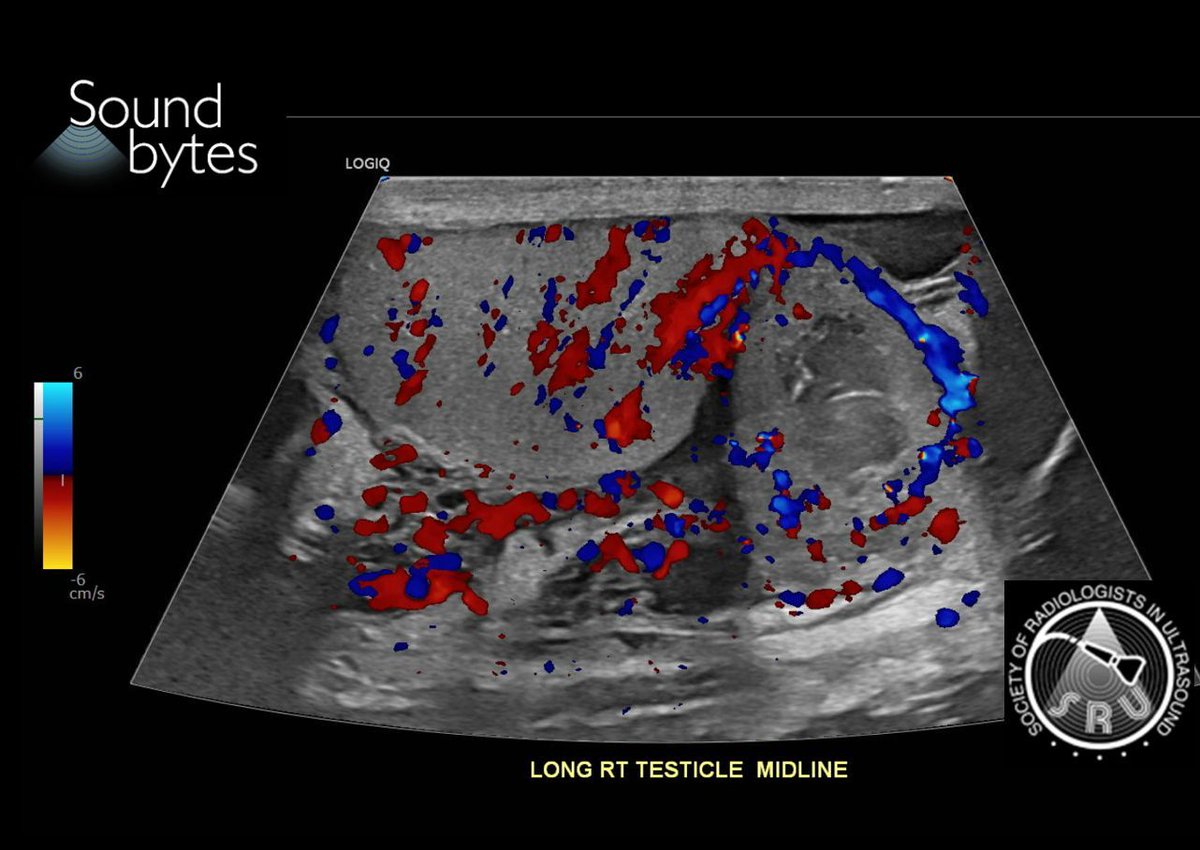

71 yo man with persistent right scrotal pain and swelling. What is your sound diagnosis?

Case courtesy of Drs. Boyan Fan and Marta Flory, Stanford University